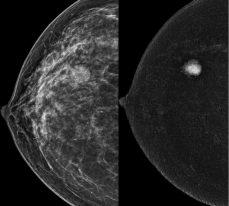

OPHTHALMOLOGY CLAIMS

Defending claims is eye-watering

Claims experts Claire Wratten and Pete Renwick (right) discuss what is to be learned from the claims they have received from ophthalmology members of the Medical Defence Union (MDU)

THE MDU regularly assists ophthalmologists with a variety of issues ranging from regulatory matters and inquests to complaints and medico-legal or ethical scenarios.

Many ophthalmologists work in private practice and this review focuses on the last ten years of experience in handling clinical negligence claims against ophthalmology members (see box on top of opposite page).

The most common reason for a claim was following cataract surgery.

Claims were often brought when the wrong lens had been used. Another common allegation was that the consent process had been inadequate and that the claimant had not anticipated they might continue to need glasses following surgery.

Claims were also brought follow-

ing postoperative complications such as glaucoma, retinal detachment, retained lens fragments and endophthalmitis.

There were a significant number of claims in relation to refractive surgery. Slightly more of these related to lens surgery than laser surgery, although both primarily occurred due to an alleged failure of the treatment or postoperative complications.

These issues often arose due to alleged failures to correctly assess suitability for treatment, alleged failure to obtain accurate optical values prior to surgery and alleged inappropriate choice of treatment.

Postoperative concerns and complications included an on-going need to wear glasses, corneal damage and dry eye syndrome.

There were also several claims related to lens surgery performed

for age-related macular degeneration, which concerned allegations about consent and, in particular, failing to advise the patient that they were not a suitable candidate for the surgery and an unsatisfactory outcome in terms of improvement in vision.

The primary cause of claims following blepharoplasty was postoperative scarring. Other issues raised were postoperative pain, blurred vision and a failure to pick up on other conditions.

Additional cosmetic procedures that were subject to claims included corneal tattooing, surgery to remove molluscum contagiosum and fat transfer procedures.

The majority of claims relating to an alleged delay in diagnosis were due to an alleged delay in diagnosis of an intracerebral

tumour, including prolactinomas, meningiomas or glioblastomas, or an alleged delay in diagnosis of glaucoma.

The potential for claims against ophthalmologists following diagnosis of an extra-ocular condition highlights the importance of examining the eyes holistically and considering pathology outside of the eye as a cause for visual impairment.